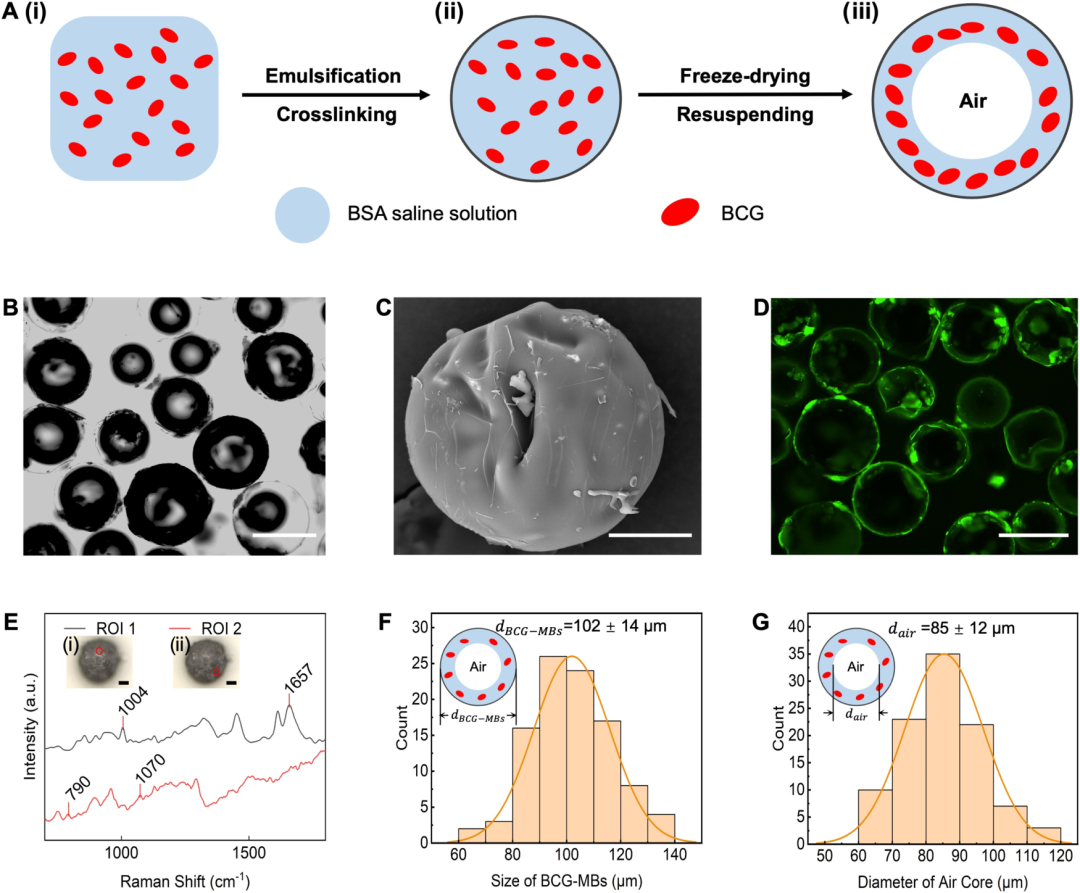

本研究聚焦于解决膀胱癌免疫治疗中的关键瓶颈问题——卡介苗(BCG)在膀胱内滞留时间过短的挑战。研究团队创新性地开发了一种基于浮动空气微气泡的药物递送系统(BCG-MBs),通过将BCG封装在特制的微气泡中,使其能够稳定漂浮在尿液表面而不随排尿被迅速排出,从而实现BCG在膀胱内的长期滞留和持续释放。这种微气泡系统采用乳化、交联和冷冻干燥的策略制备,形成具有三层结构(内层空气核心、中间溶液层和外层壳)的微球,其平均尺寸为102微米,内部空气核心直径约85微米,平均密度仅为509.82 kg/m³,远低于尿液密度,确保了其在膀胱内的漂浮特性。这一设计巧妙利用了物理浮力原理,避免了传统粘附性水凝胶可能干扰膀胱正常生理功能的缺陷,也无需依赖复杂的外部磁场设备。

图 BCG-MBs的制备与表征

台式扫描电镜在本研究中发挥了关键的表征作用,为微气泡系统的结构验证提供了直观而精确的证据。研究团队使用188博金宝网页官网ZEM18台式扫描电镜对冻干后的BCG-MBs进行金溅射镀膜处理后,在不同放大倍数下观察其表面形态,清晰地展示了微气泡规则的球形结构以及BCG在微气泡表面的不规则分布状态。这一表征不仅确认了微气泡制备工艺的成功,还直观揭示了BCG在微气泡中的物理分布特征,为理解药物释放机制提供了结构基础。扫描电镜图像作为重要的形态学证据,有力支持了后续对微气泡浮力特性、药物释放行为及生物效应的分析,是连接材料设计与功能验证的关键环节。